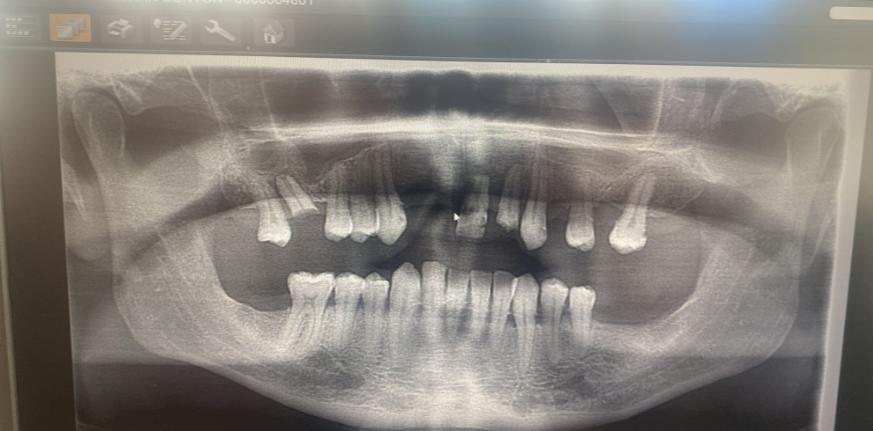

Un bărbat care a crezut că-și repară toată dantura cu 5.000 de euro în Turcia s-a întors acasă fără niciun dinte în gură

Jon Denton avea probleme dentare din 2020, în urma unui accident rutier FOTO: GoFundMe